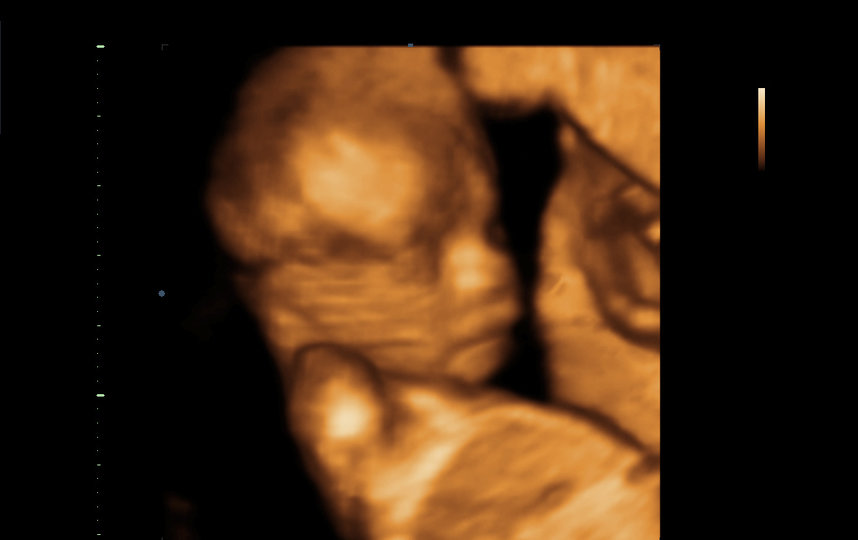

– Мама – моя лучшая подруга! – воскликнула Бреанна. – Я плачу каждый раз, когда вижу малыша на ультразвуке. Это невероятные эмоции! Я люблю трогать её живот. Она каждый раз кричит, чтобы я поскорее к ней бежала, и даёт почувствовать, как девочка толкается. Едва слыша, как мама зовёт меня, я бросаю всё и мчусь к ней. Это потрясающе и нереально.